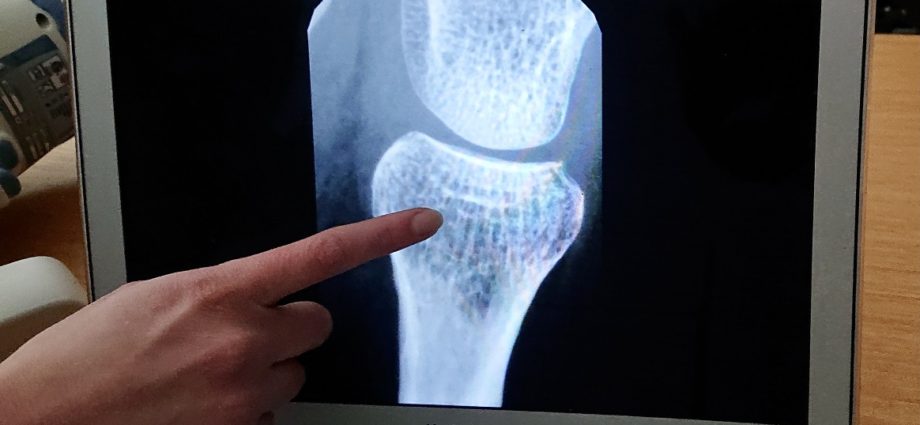

Con l’aumento dell’aspettativa di vita, è sempre più urgente affrontare la sfida di trattare i disturbi legati all’età come l’osteoporosi.

La malattia può progredire fino a disabilità significative, come fratture dell’anca e della colonna vertebrale, e comportare oneri finanziari, come la perdita di ore lavorative e il ricovero in ospedale.